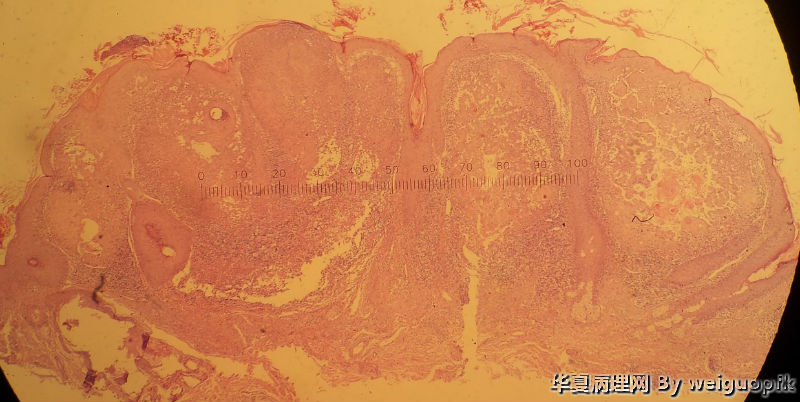

男性患者,52岁。鼻根部增生物3月余,无自觉症状。

自述3月前鼻根部出现一黑褐色丘疹,自行抠掉后,很快又有新生物长出,并逐渐增大。